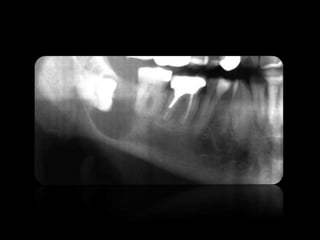

6.

CARIES